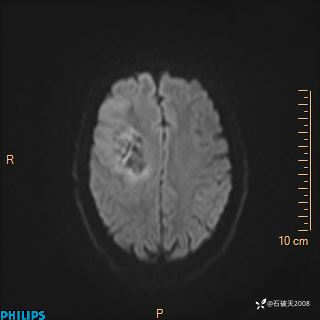

2024.2.21MR

DWI